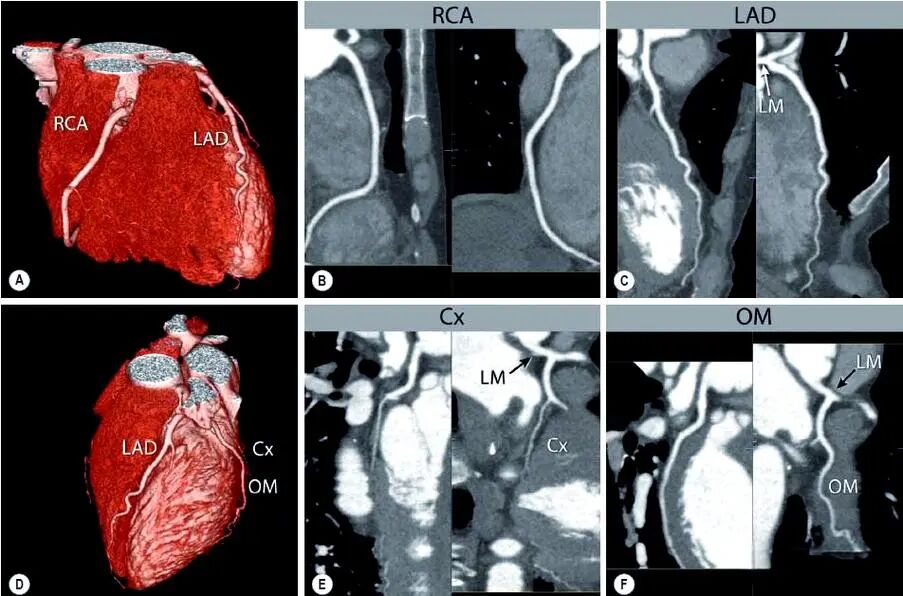

别被“CT”吓到,其实它比很多检查都简单。一个无创、无痛的高分辨率成像技术,能立体还原你冠状动脉的全貌。

做完后,医生可以直观看到血管内有没有斑块,斑块大小、位置、是否钙化,以及有没有引发血管狭窄。

冠脉CT就是“拍”出看得见的实景图,甚至比开刀看病灶还准。据《中华心血管病杂志》统计,即使是早期无症状的患者,有斑块者3年内发生心脑血管事件的风险,是无斑块者的10倍以上。